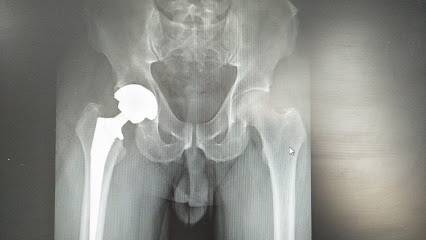

جراح استبدال مفصل الورك والركبة – الدكتور بيسواجيت باروح – مسقط – +968 7154 5984 عيادة العظام – عمان – مسقط